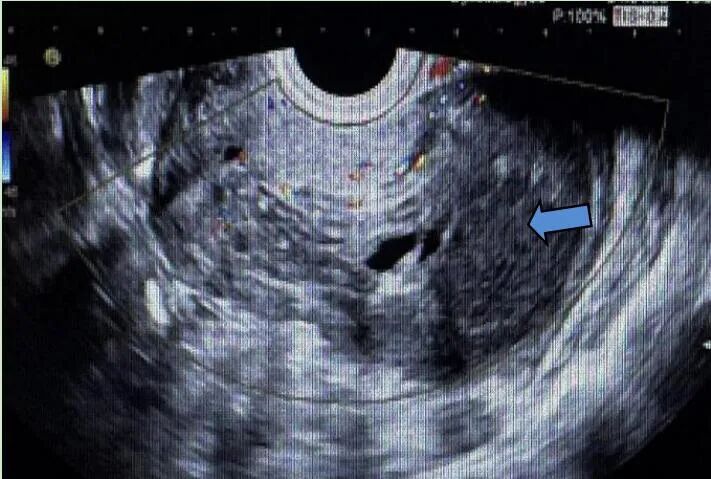

距首次手术后3个月,复查超声见子宫体大小约6.7 cm×7.0 cm×6.0 cm,肌层回声不均质,后壁突向宫腔见低回声,范围约2.5 cm×1.8 cm×1.6 cm;CDFI示周边及内部均可见点条状血流信号,宫腔居中,可疑子宫肌瘤复发。

距首次手术后半年,复查超声见子宫体大小约6.3 cm×7.1 cm×6.1 cm,肌层回声不均质,后壁为著,后壁突向宫腔见低回声,范围约2.2 cm×2.5 cm×1.9 cm;CDFI示周边及内部均可见点条状血流信号,宫腔受压前移,子宫内膜厚1.2 cm,回声不均。结合临床病史,考虑子宫肌瘤复发。